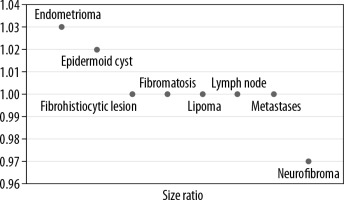

Subsequently, strain elastography was performed to evaluate the size ratio (Figure 3) and strain ratio. Elastography could be performed in 48 lesions; the rest of the lesions were either cystic or vascular in nature. Of these 48 lesions the strain ratio was calculated in all, whereas the size ratio could not be evaluated in 10 lesions due to their larger size in comparison to the probe. The average strain ratio of the lesions in this series was 1.72 ± 0.94 with a wide variability amongst the different pathologies (Figure 4).